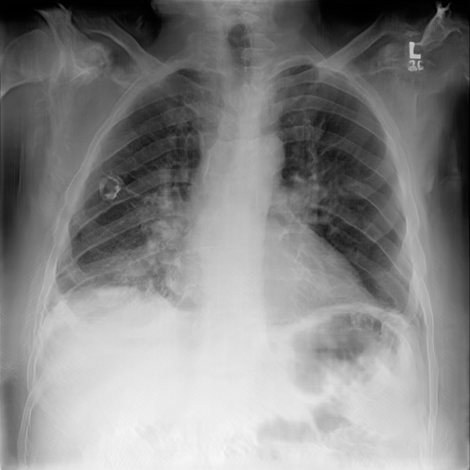

We used the NIH Chest X-ray 14 [73] dataset to conduct our experiments. This dataset consists of labeled chest X-ray images, from over unique patients corresponding to 14 common thoracic disease types, including atelectasis, cardiomegaly, effusion, infiltration, mass, nodule, pneumonia, pneumothorax, consolidation, edema, emphysema, fibrosis, pleural thickening, and hernia. The dataset is divided into training, validation, and testing sets, containing , . and images, respectively444We followed the dataset splits in https://github.com/zoogzog/chexnet/tree/master/dataset. Our experiments were designed to examine and compare four training methods:

Figure 7 samples real and GAN-generated images. The first column presents real images, the second column GAN-generated unsupervised, and the third GAN-generated supervised. The GAN-generated images may successfully fool our colleagues with no medical knowledge. However, as reported in [63], the GAN-generated labeled chest X-ray images must be screened by a team of radiologists to remove erroneous data (with respect to diagnosis knowledge). Without domain knowledge, incorrectly labeled images may be introduced by GANs into the training pool, which would degrade classification accuracy.

| Real | GAN unsupervised | GAN supervised |